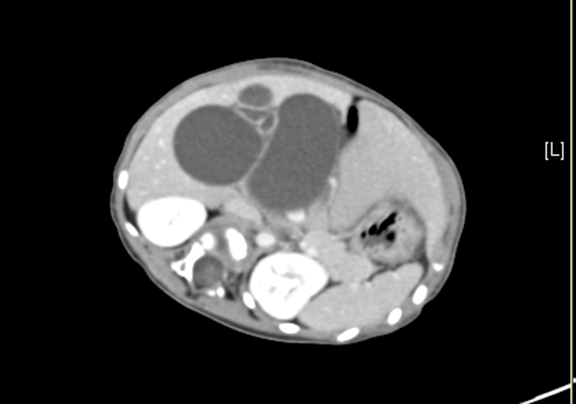

上腹部增强CT:符合胆总管囊肿。

将0.625mm双源薄层CT资料的静脉期和动脉期Dicom格式文件导入海信CAS系统。

通过调节窗宽窗位调整CT序号,对肝实质,胆囊,胆总管,下腔静脉,肝动脉、门静脉及肝静脉等进行三维重建;系统自动计算肝脏体积。

术前CT检查:

动脉期

静脉期

平衡期